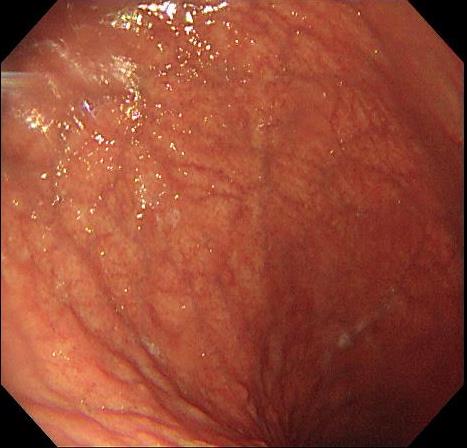

摘要:目的 探讨利那洛肽联合西甲硅油与复方聚乙二醇电解质散(PEG)对便秘患者肠道清洁效果的有效性和安全性。方法 采用前瞻性随机对照试验,通过单盲法,纳入2023年4月-2024年8月于该院消化内镜中心行结肠镜检查的便秘患者383例,随机分为常规组(128例)、实验A组(128例)和实验B组(127例)。常规组采用3 L PEG(Ⅰ)溶液,实验A组采用290 μg利那洛肽 + 2 L PEG溶液,实验B组采用290 μg利那洛肽 + 30 mL西甲硅油+2 L PEG溶液。比较3组患者的肠道准备效果[Boston肠道准备量表(BBPS)评分和去泡效果]、病变检出率、首次排便间隔时间、排便次数、盲肠插管成功率、进镜时间、退镜时间、不良反应发生率和重复检查意愿等。结果 3组患者BBPS评分比较,差异无统计学意义(P > 0.05);实验B组的去泡效果评分明显低于常规组和实验A组,差异均有统计学意义(P < 0.05);实验B组的病变总检出率和息肉检出率明显高于常规组和实验A组,差异均有统计学意义(P < 0.05);常规组的首次排便间隔时间明显长于实验A组和实验B组,差异均有统计学意义(P < 0.05);3组患者排便次数比较,差异无统计学意义(P > 0.05);3组患者盲肠插管成功率均为100.0%,进镜时间相当,差异均无统计学意义(P > 0.05);实验B组的退镜时间明显短于常规组和实验A组,差异均有统计学意义(P < 0.05);常规组腹胀腹痛发生率和不良反应总发生率明显高于实验A组和实验B组,差异均有统计学意义(P < 0.05);常规组重复检查意愿率明显低于实验A组和实验B组,差异均有统计学意义(P < 0.05)。结论 290 μg利那洛肽联合30 mL西甲硅油与2 L PEG溶液方案在便秘患者肠道准备上具有优势,较3 L PEG溶液和290 μg利那洛肽+2 L PEG溶液方案,可获得更好的肠道清洁效果,且安全性和患者重复检查意愿率高,可作为便秘患者肠道准备的推荐方案。

• 不同时机聚乙二醇电解质散剂给药方案对肠道清洁效果的影响

2025, 31(6):64-69. DOI: 10.12235/E20250151

摘要 (370) HTML (185) PDF 704.43 K (135) 评论 (0) 收藏

摘要:目的 探讨无痛结肠镜前顿服与不同剂量间隔12 h分次口服聚乙二醇电解质散剂(PEG)对肠道清洁效果的影响,以期优化肠道准备方案,提高患者的耐受性。方法 选择2024年6月-2024年9月在该院消化内科内镜中心接受无痛结肠镜检查,并使用PEG作为肠道清洁剂的患者232例作为研究对象。将参与者分为3组:对照组(3.00 L PEG顿服组)、试验A组(0.75 L+2.25 L PEG组)和试验B组(1.50 L+1.50 L PEG组),所有患者均在服用完毕后4 ~ 6 h内进行无痛结肠镜检查。其中,试验A组和试验B组两次服用PEG的间隔时间均为12 h。通过波士顿肠道准备评分(BBPS)评估肠道清洁度,并记录结肠息肉检出率、患者不良反应、睡眠时间及耐受性。结果 3组患者BBPS评分和结肠息肉检出率比较,差异均无统计学意义(P > 0.05)。试验B组服用PEG后的不良反应最轻,其次是试验A组,对照组的不良反应最明显(P < 0.05)。不同时间口服PEG对3组患者的睡眠时间无明显影响(P > 0.05)。试验B组对PEG的耐受性良好,愿意接受此方案进行肠道准备,试验A组次之,对照组耐受性最差,3组之间比较,差异有统计学意义(P < 0.05)。结论 顿服与分次服用PEG对肠道清洁效果及结肠息肉检出率无明显影响,但间隔12 h分次PEG方案,患者不良反应轻、耐受性好,尤其是间隔12 h分2次服用1.50 L PEG方案最佳。